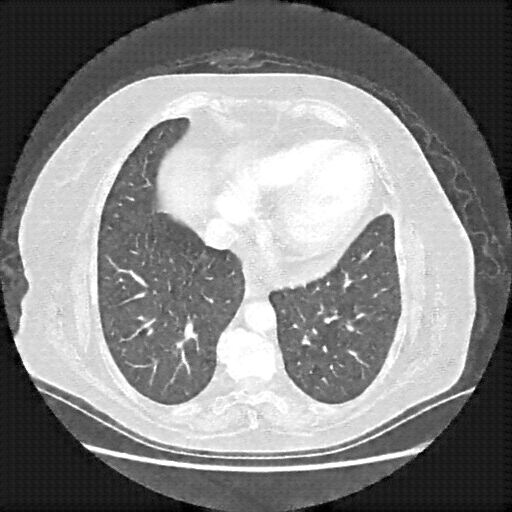

Reconstructed NATIVE CT scan (cycle consistency)

Full window (WL 1023.5, WW 4095 β†’ Low βˆ’1024, High +3071)

Lung window (WL -600, WW 1500 β†’ Low βˆ’1350, High +150)